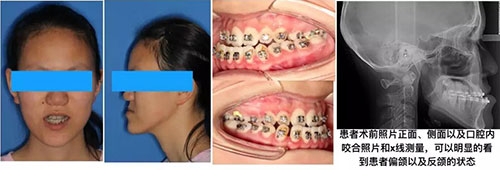

颌面部应重点检查颞下颌关节、上颌骨与下颌骨、颌骨与颅基底的侧向(前后)、横向(左右)、垂直向(上下)的大小、比例等颅颌面关系,并进行口颌系统的功能检查等。获取病人的牙(牙合)模型,是对牙颌面畸形进行诊断分析、治疗及疗效评估不可缺少的重要资料。综合对正面、侧貌、唇形以及颌关系等,进行三维形态的美学评估,初步勾画出病人颅面畸形的轮廓印象。

X线片是确定诊断及治疗计划的重要步骤和依据,在必要时,可摄取颅颌三维CT片以及单独显示颌骨及颞下颌关节,亦可采用计算机辅助头影测量分析,或面部摄影测量及颜面摩尔条纹测量,观察其细微空间结构变化,作为较为精确的测量分析。